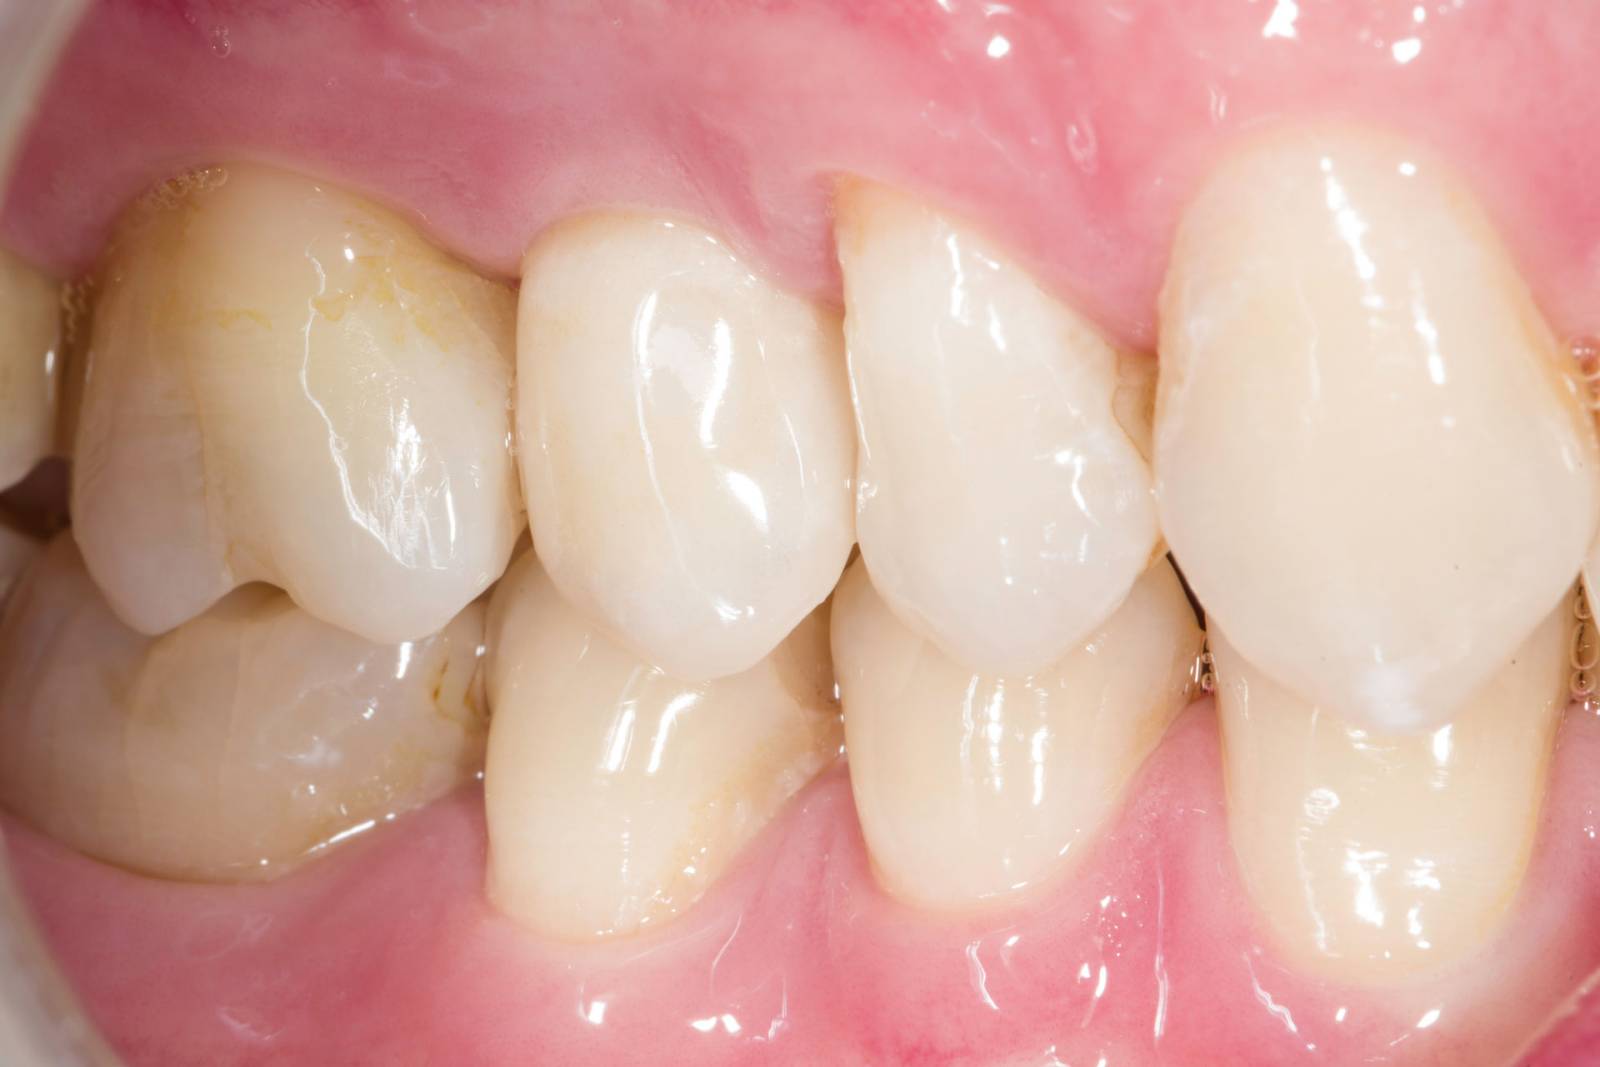

Before

Insufficient fillings in the second quadrant. The restorations were about 15 years old.

After

Chairside-fabricated crowns made from CEREC Tessera (teeth 26/27). Inlays for teeth 24 and 25 made of composite blocks.